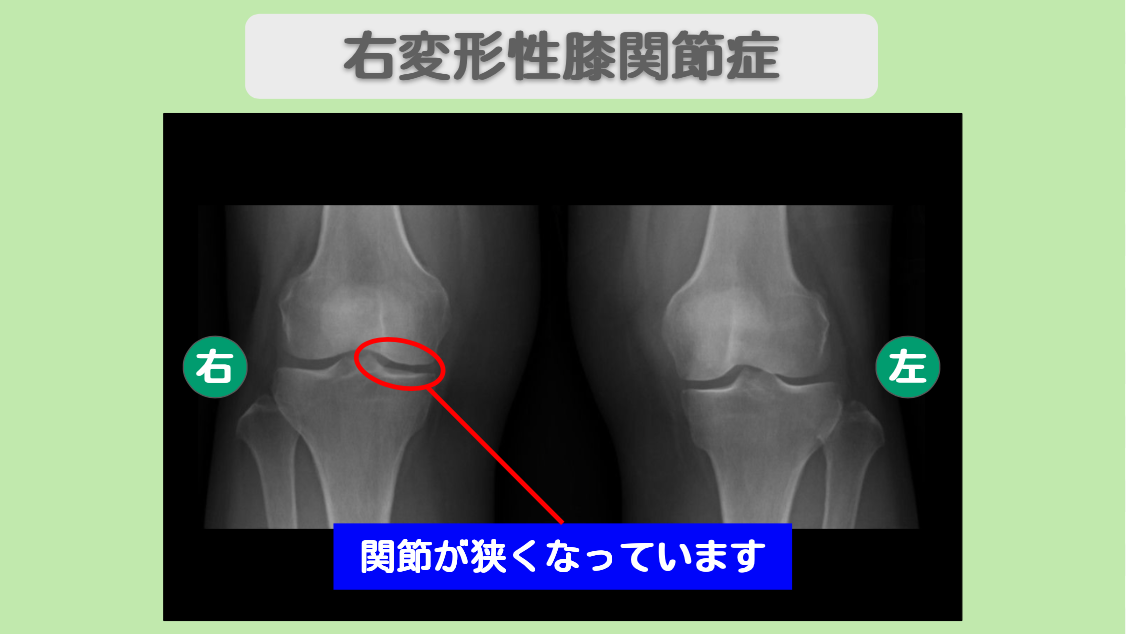

MRI・レントゲン所見

MRIにて半月板の損傷を認めます。